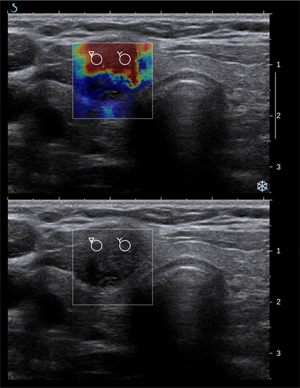

Papillary thyroid carcinoma on elastography (top) and ultrasonography (bottom); source: Wikimedia Commons, Oreo Priest